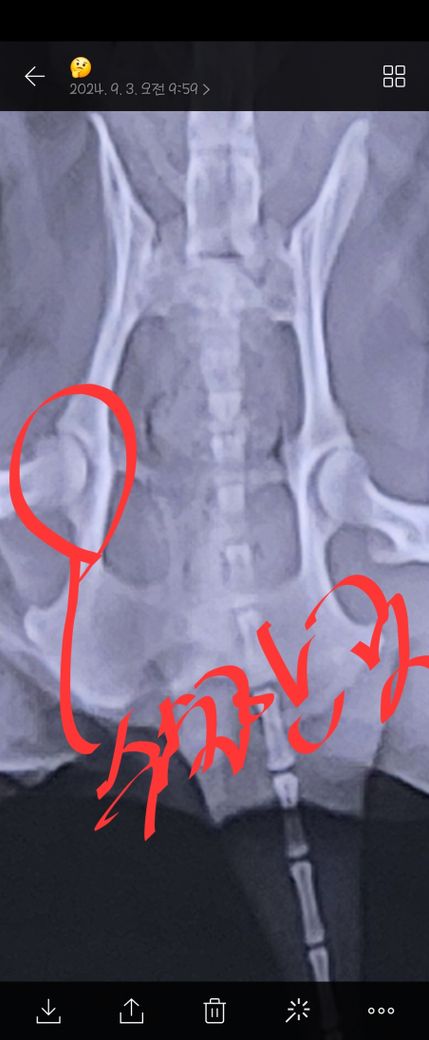

14일쯤 고관절에 핀을 박고 일주일전쯤 핀 제거하고 어제 실밥도 제거했습니다. 그런데 밤 부터 깽깽이발로 다녀요.

핀 뽑는 날 엑스레이 사진입니다.